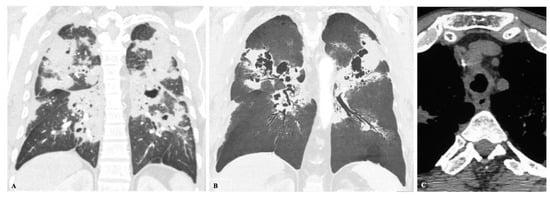

2.4. Disseminated Infection

2.5. Mixed Pattern